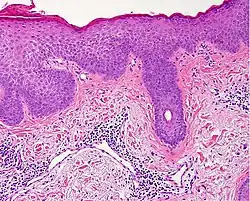

Generally/Not otherwise specified Typical findings, called "vacuolar interface dermatitis":[6]

• Mild inflammatory cell infiltrate along the dermoepidermal junction (black arrow in image)

• Vacuolization within the basal keratinocytes (white arrow in image)

• Often necrotic, predominantly basal, individual keratinocytes, manifesting as colloid or Civatte bodies

Acute graft-versus-host-disease

• Vacuolar alteration of various severity, from focal or diffuse vacuolation of the basal keratinocytes (grade I), to separation at the dermoepidermal junction (grade III)

• Involvement of the hair follicle[6]

• Rarely eosinophils[6]

Allergic drug reaction

• Rarely involvement of hair follicles.[6]

• Frequently eosinophils[6]

Lichen sclerosus Hyperkeratosis, atrophic epidermis, sclerosis of dermis and dermal lymphocytes.[7]